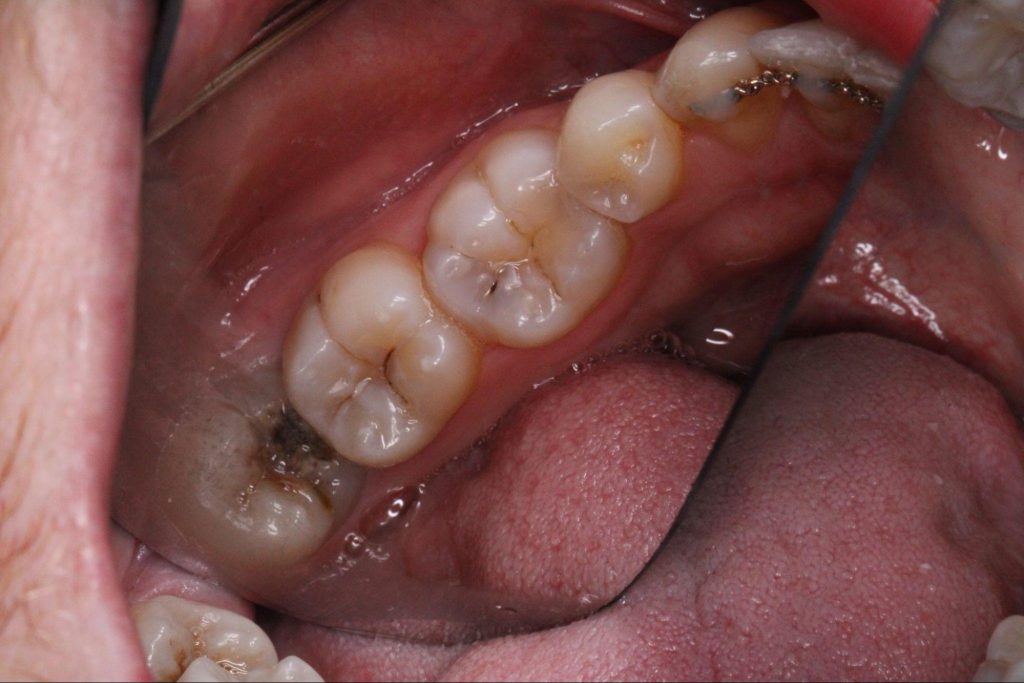

Wisdom teeth are the last molars to develop, and by the time they appear there is often limited space in the jaw. Because of this, they frequently grow sideways, remain partially impacted, or press against the adjacent molar. This positioning makes the area extremely difficult to clean properly (as you see in the image below).

When bacteria accumulate between a wisdom tooth and the neighboring molar, plaque and decay can develop in a location that is almost impossible to reach with regular brushing and flossing. Even patients with excellent oral hygiene may struggle to maintain this area because of the tooth’s angle and the limited space.

As decay progresses, it may affect both teeth at the same time. In many cases the wisdom tooth was never functioning properly to begin with, but the healthy molar beside it may also become compromised if the issue is not addressed early.